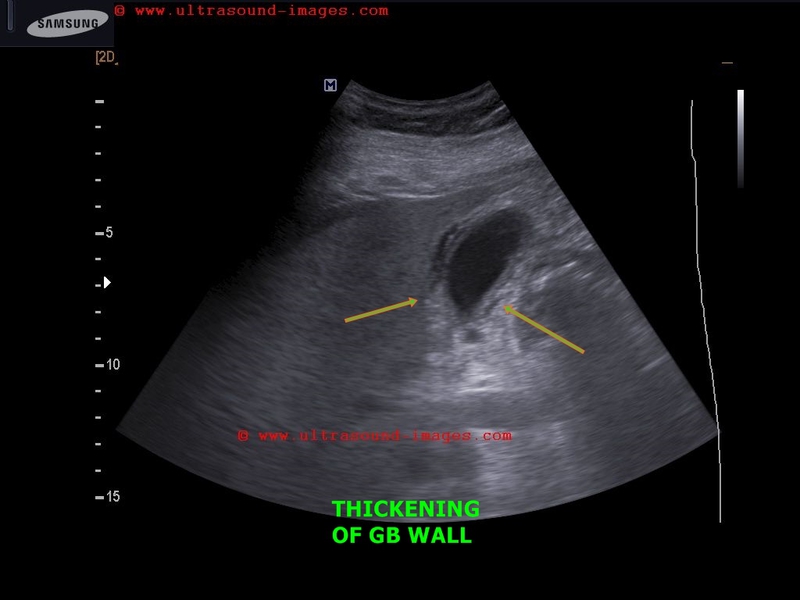

gallbladder-wall-thickening-dengue

This 50 yr female patient had abdominal pain and was clinically diagnosed to be suffering from dengue.

Ultrasound scan shows- minimal free fluid near right lobe of liver

- thickening of gallbladder wall (more than 7mm. in this case)

- striated pattern of gallbladder wall

- lack of abnormal or increased vascular flow in GB on Power        Doppler study.

Increased thickness of gallbladder wall is a common ocurrence in dengue as multiple studies have shown.

There are reported to be 5 different varieties of GB wall thickening in dengue as imaged on sonography.

a) uniformly echogenic layer

b) striated pattern (as in this case)

c) tram track pattern

d) honeycomb pattern

e) focal thickening

(We used a Samsung Acuvix ultrasound system to capture these images).